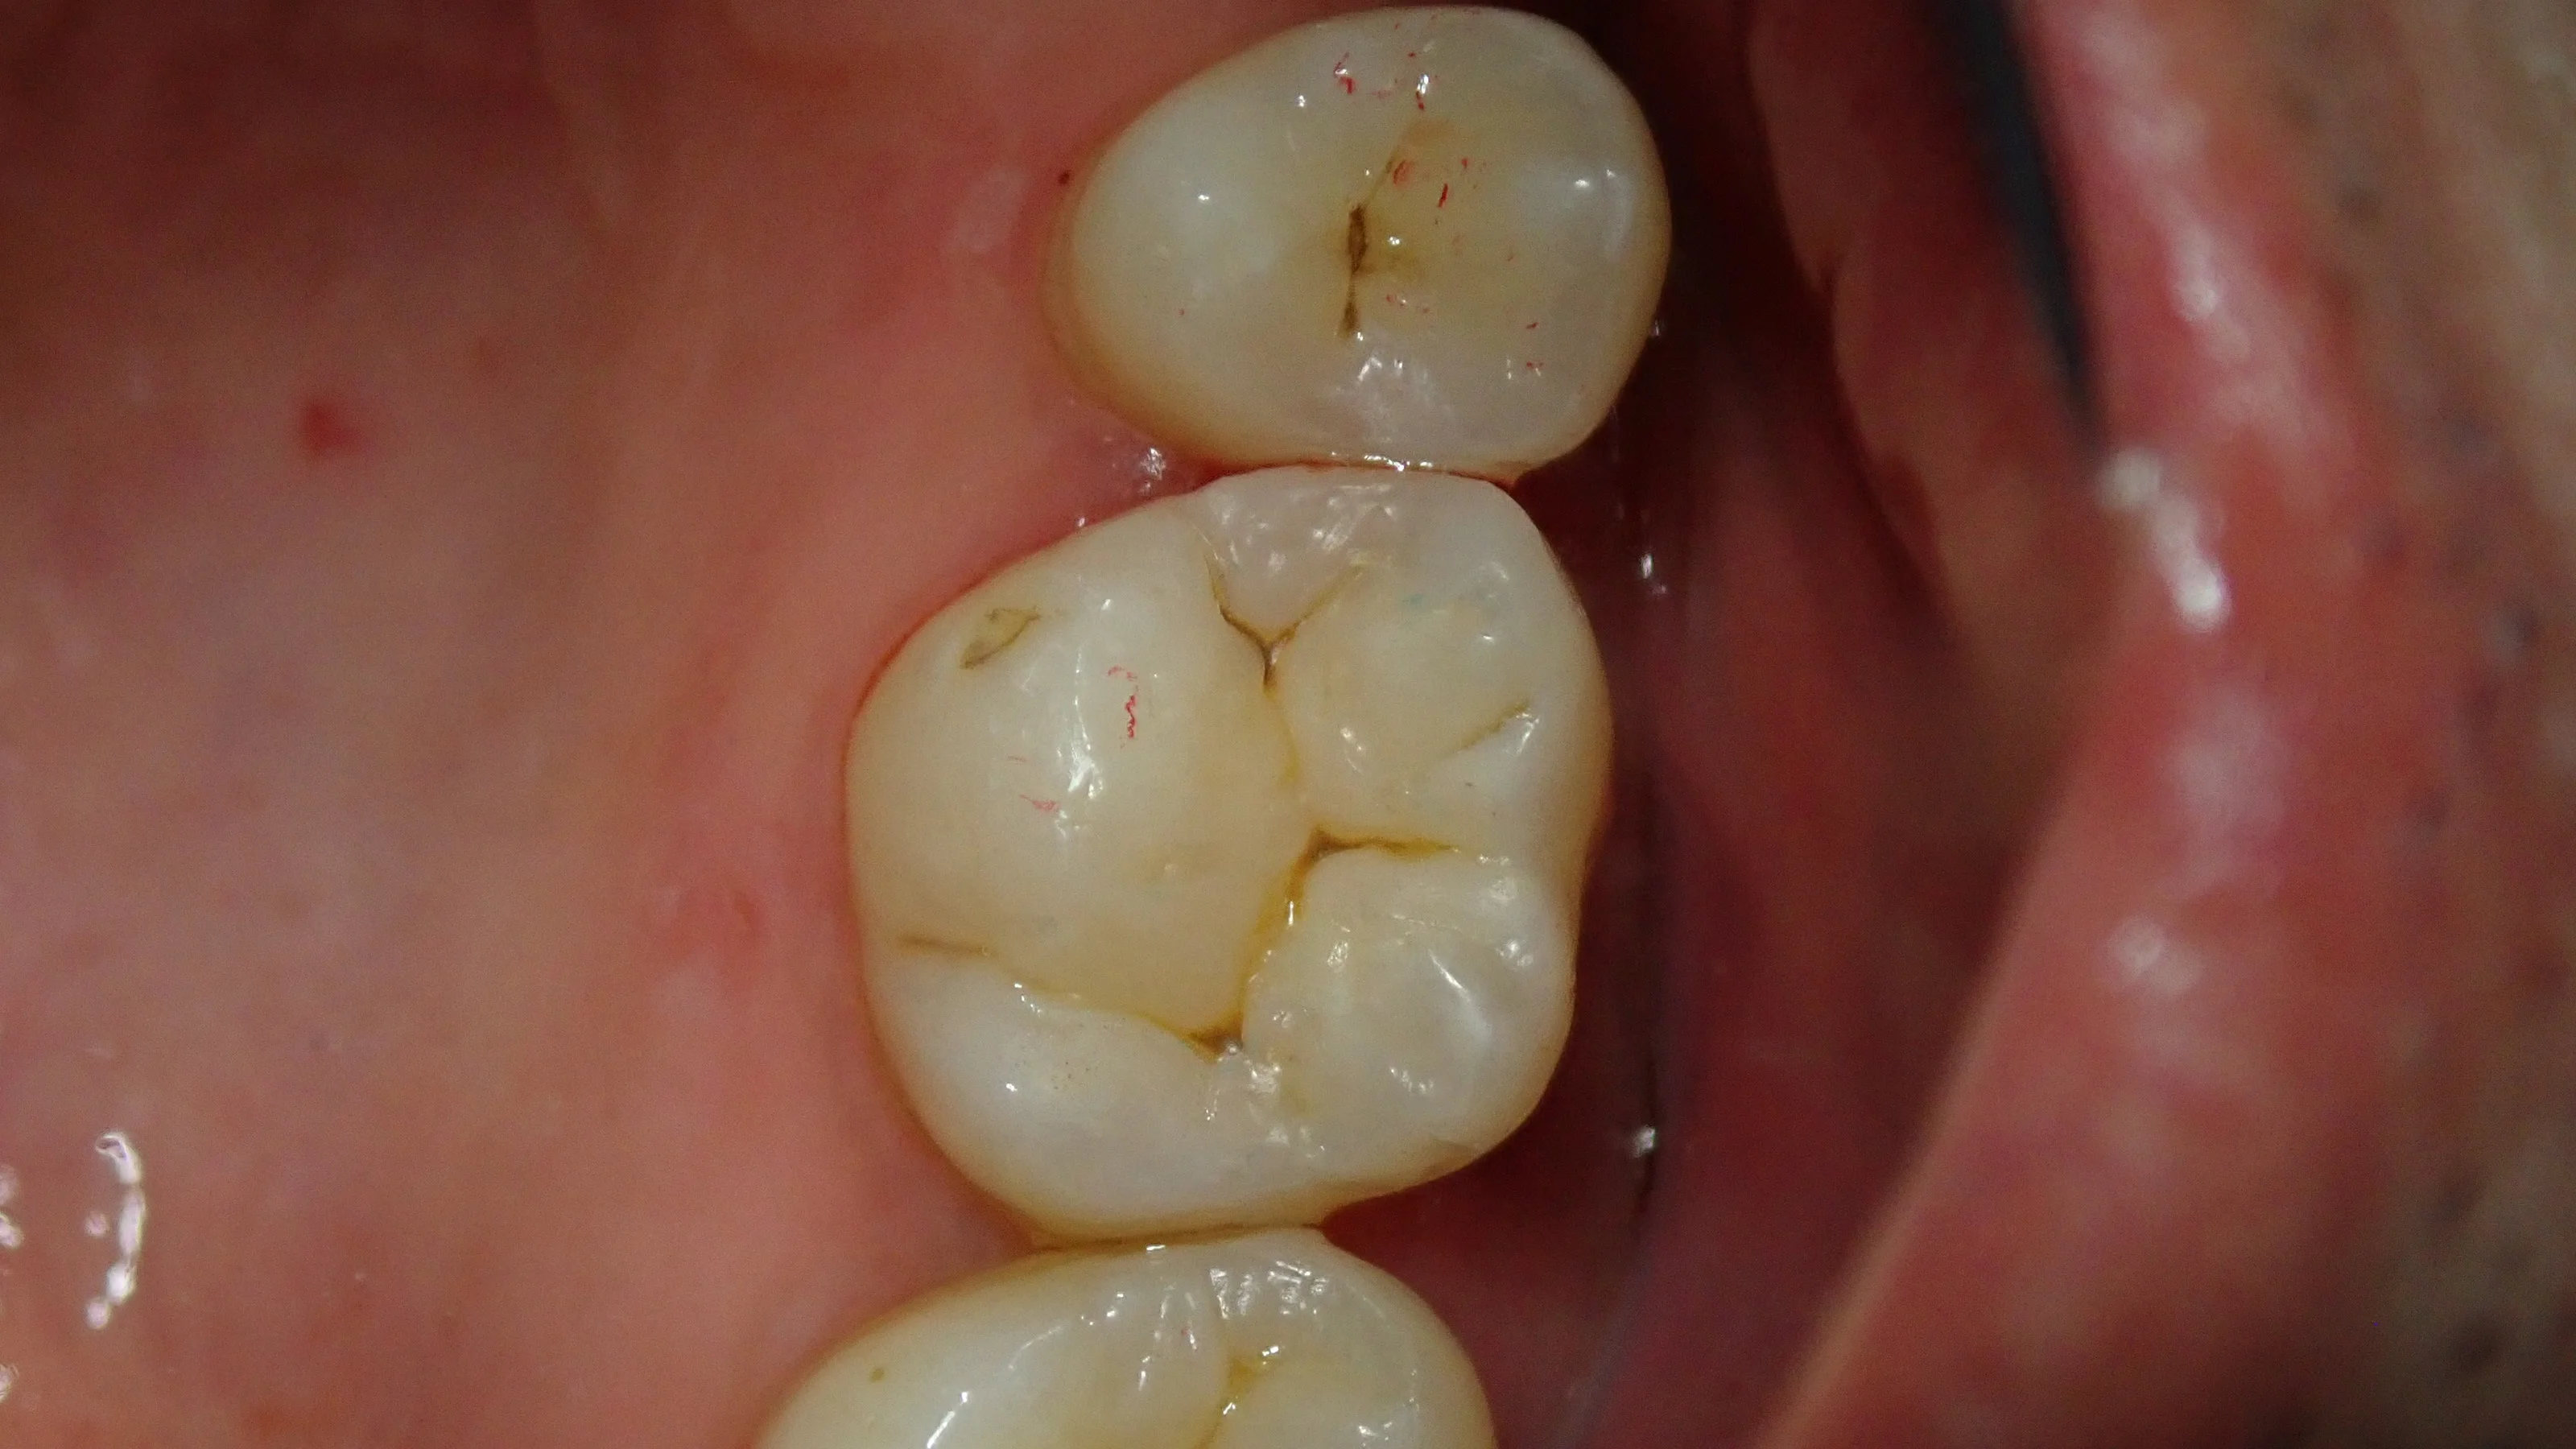

ひとまず、虫歯を取り切った時の画像がこちらです。

画像上でみてもらうと分かりますが、インレーというものは通常の虫歯部分に比べて非常に大きく削ります。

その最たる箇所が、隣接面(前後の歯との間)です。

特にメタルインレーの場合は非常に大きく、容赦なくスライスカットを入れることが多いです・・・。

この大きくスライスカットを入れられた歯をダイレクトボンディングで修復した結果・・・

こうなりました。

スライスカットの説明の際に使用した画像なんです(笑)

術後写真をそのまま説明に利用させてもらいました( ´艸`)